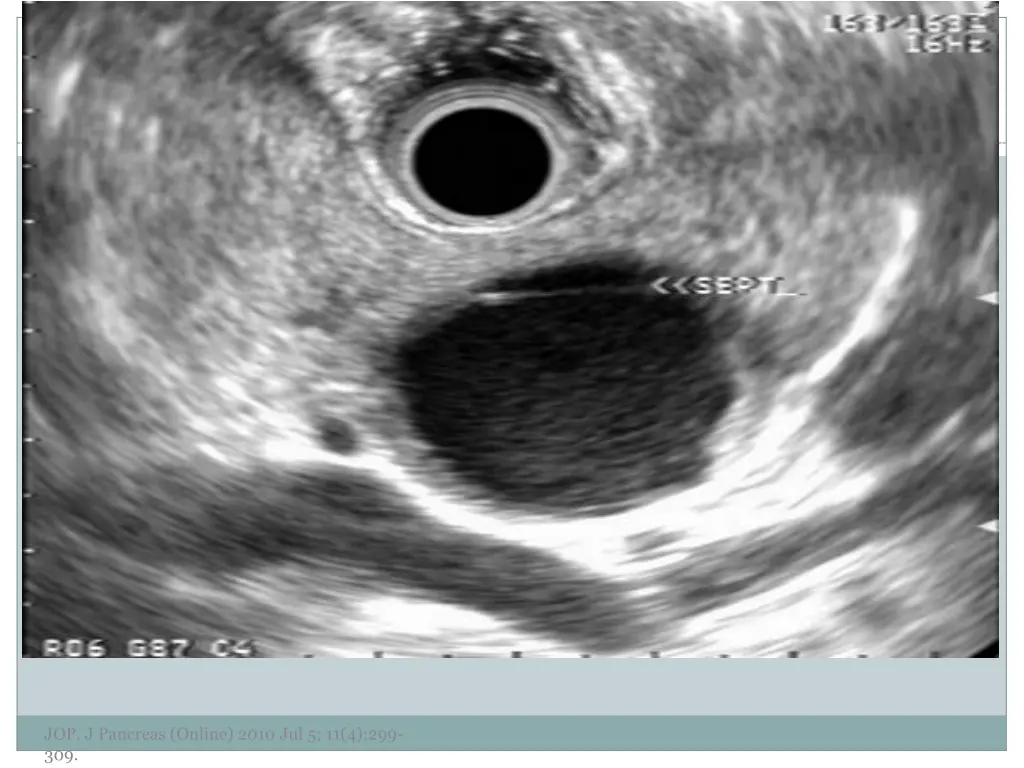

7. EUS Morphology Cyst wall Thick vs. thin Solid component Associated with malignancy Septations Micro vs. macrocystic Ductal abnormalities Main duct vs. side duct Number of cyst Lymphadenopathy EUS morphology can correctly differentiate mucinous from non-mucinous cystic lesions approximately 50% of the time JOP. J Pancreas (Online) 2010 Jul 5; 11(4):299- 309.

11. JOP. J Pancreas (Online) 2010 Jul 5; 11(4):299- 309.